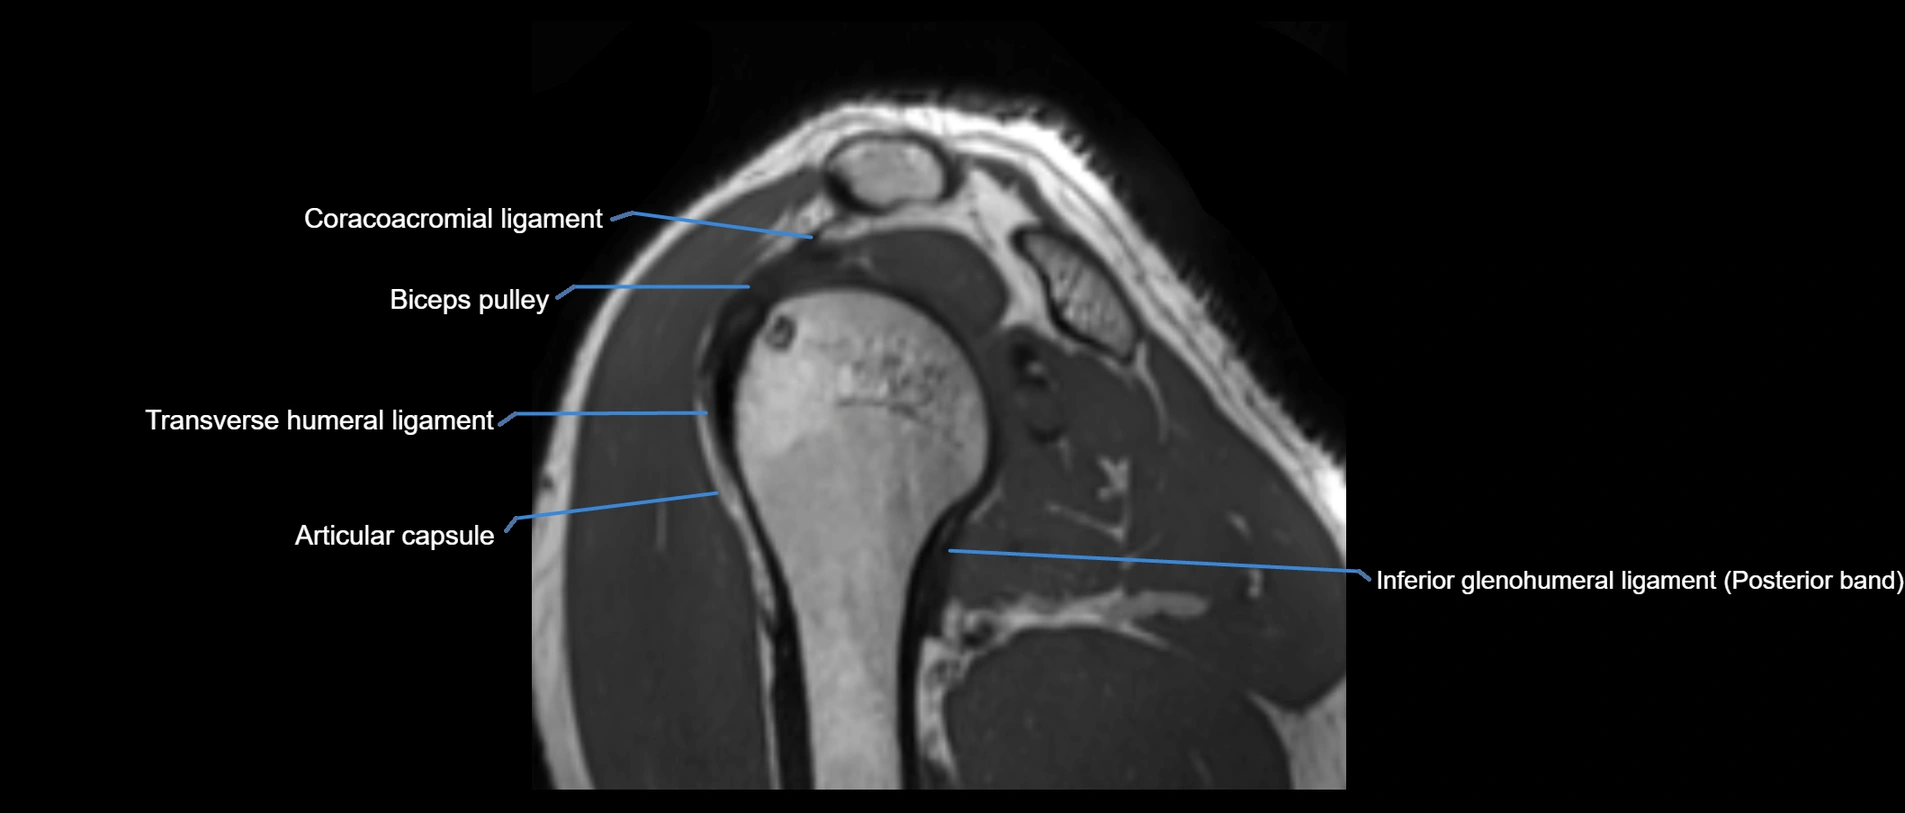

MRI Appearance

• T1-weighted images:

• Normal ligament: Low signal (dark linear band) spanning acromion to clavicle.

• Surrounding fat planes: Bright, delineating the ligament clearly.

• T2-weighted images:

• Normal ligament: Low signal, homogeneous.

• Proton Density Fat-Saturated (PD FS):

• Normal ligament: Low signal, uniform thickness.

• Partial tear or sprain: Bright signal or contour irregularity.

• Complete tear: Clear discontinuity with bright signal gap and joint effusion.

MRI images

image